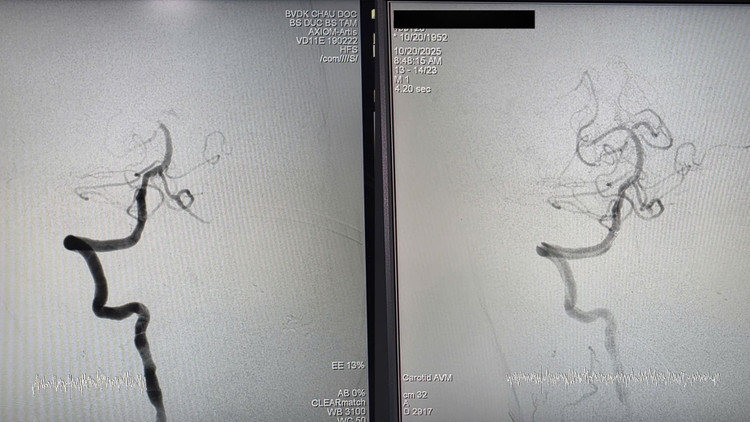

than-nen-c.jpg

Hình ảnh trước và sau can thiệp - Ảnh BVCC